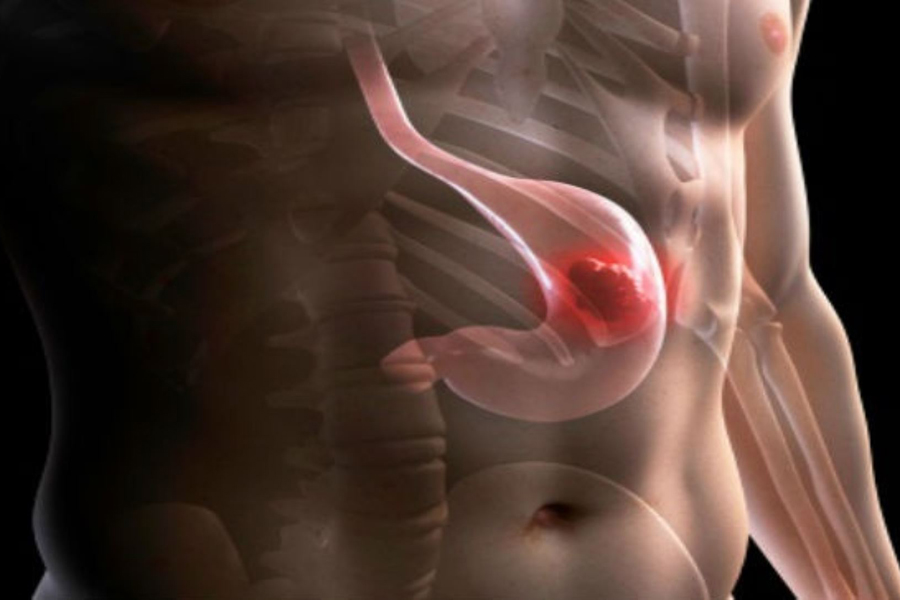

La tendencia a nivel mundial en el tratamiento del cáncer gástrico incluye planes de quimioterapia neoadyuvante, para mejorar la resecabilidad, disminuir la recidiva locorregional, mejorar la calidad de vida y aumentar el tiempo libre de enfermedad.

El hinchazón del epigastrio por gas tras una intervención por reflujo gastroesofágico o hernia de hiato, comprende un grupo de quejas mal definidas y variables que se supone resultan de la dificultad para eructar.

Para la cirugía de la obesidad es aconsejable realizar una preparación previa con la finalidad de disminuir peso, reducir el volumen del hígado y prevenir fenómenos tromboembólicos. ¿en que consiste esta preparación? y sobre todo, ¿cuando y como tenemos que hacerla?